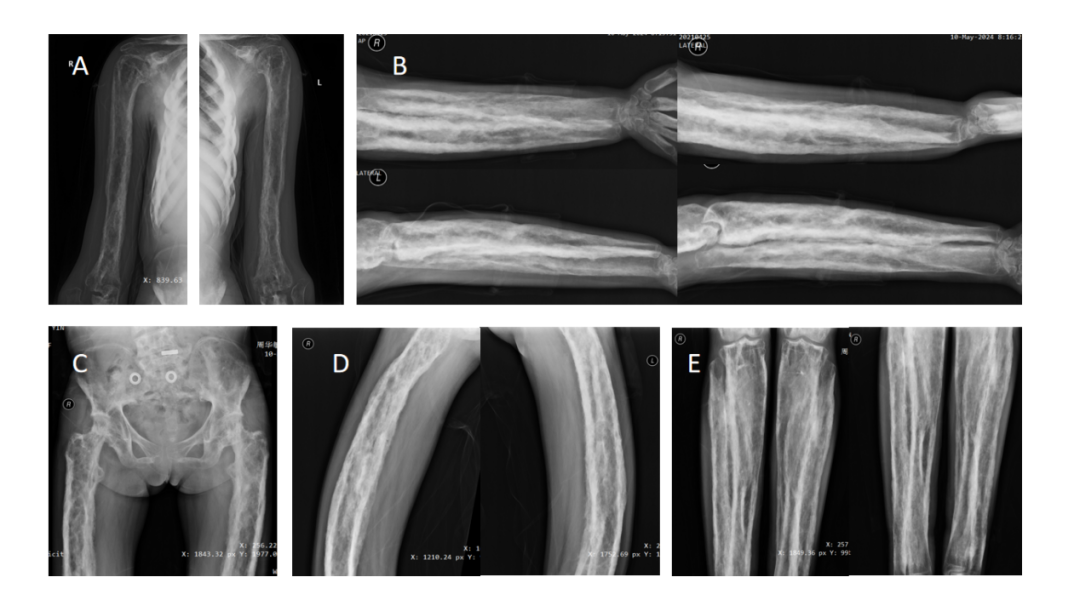

近日,“医学界”从上海交通大学医学院附属第九人民医院(下称“九院”)获悉,该院诊断出一例发病率仅百万分之一的罕见遗传性骨病。据了解,这是一名年轻女性,因双眼突出及视力下降,前往九院眼科就诊。除眼部异常外,她还同时伴有长期四肢骨痛、听力下降等全身表现。接到患者后,九院眼科迅速组织内分泌科、分子诊断科、骨科、影像科、耳鼻喉科等开展多学科联合会诊,最终确诊为Camurati-Engelmann病(进行性骨干发育不良)。该病例研究已于近日在国际眼眶病领域权威期刊Orbit在线发表。据介绍,患者以双侧眼球突出伴视力下降为主要表现,同时存在长达15年的四肢骨痛及听力进行性下降。曾于外院诊断为甲状腺功能减退症及性腺功能低下。眼科检查发现,患者存在双眼上方视野轻度缺损,伴有视神经纤维层变薄。此外,眼眶CT还提示患者的视神经受压。CT显示,患者双侧眼眶骨壁弥漫性增厚,眶尖区域明显狭窄,同时可见视神经管变窄及眼上静脉扩张(见下图蓝色箭头)。这些改变提示,眶尖拥挤导致视神经受压,静脉回流受阻可能加重眶内压力,进而影响视神经供血及视觉功能。进一步全身X线检查显示,患者全身多处长骨存在双侧对称性骨干皮质增厚、骨性膨大,提示疾病并非局限于眼眶,而已经累及全身骨骼系统。从家系图可以看出,患者家族中共有包括其母亲的9名成员存在类似表现,呈现明显的家族聚集现象,提示该疾病的遗传背景。基因检测进一步证实,患者及其母亲均携带TGFB1基因致病性变异。该基因编码转化生长因子β1,在骨重塑调控中发挥关键作用,其异常可导致骨形成与吸收失衡,从而引发特征性骨干增厚。结合临床表现、血液学、影像学及遗传学证据,最终确诊为Camurati-Engelmann病。经多学科会诊,鉴于患者目前视力情况尚稳定,优先针对骨代谢异常及内分泌紊乱予以系统性治疗,并进行密切随访视功能变化。若随访过程中出现进行性视力下降或视神经损伤加重,可考虑行眼眶减压术及视神经减压术,缓解视神经压迫。值得注意的是,患者母亲在妊娠及分娩后症状曾出现明显缓解。类似现象在既往个案报道中亦有描述。提示疾病可能与激素水平变化或免疫调节机制相关,但具体机制仍有待进一步研究验证。研究作者介绍,Camurati-Engelmann病是一种罕见的常染色体显性遗传性骨代谢疾病,主要由TGFB1基因突变引起,发病率约为1/100万。其典型特征为长骨骨干皮质对称性增厚及骨重塑异常。典型临床表现为四肢骨痛、肌无力及步态异常,可伴随内分泌功能异常等全身表现。随着疾病进展,病变可累及颅骨与颅底结构,导致头痛、听力下降及视功能损害。该病临床表现异质性较大,容易造成误诊或漏诊,临床上通常需开展多学科联合诊疗,以明确诊断并指导后续治疗。上海交通大学医学院附属第九人民医院眼科周慧芳教授与内分泌科乔洁教授担任共同通讯作者,眼科博士研究生雷超宇为第一作者。分子诊断科赵双霞副研究员及眼科李寅炜副主任医师共同参与了疾病诊治和研究指导。